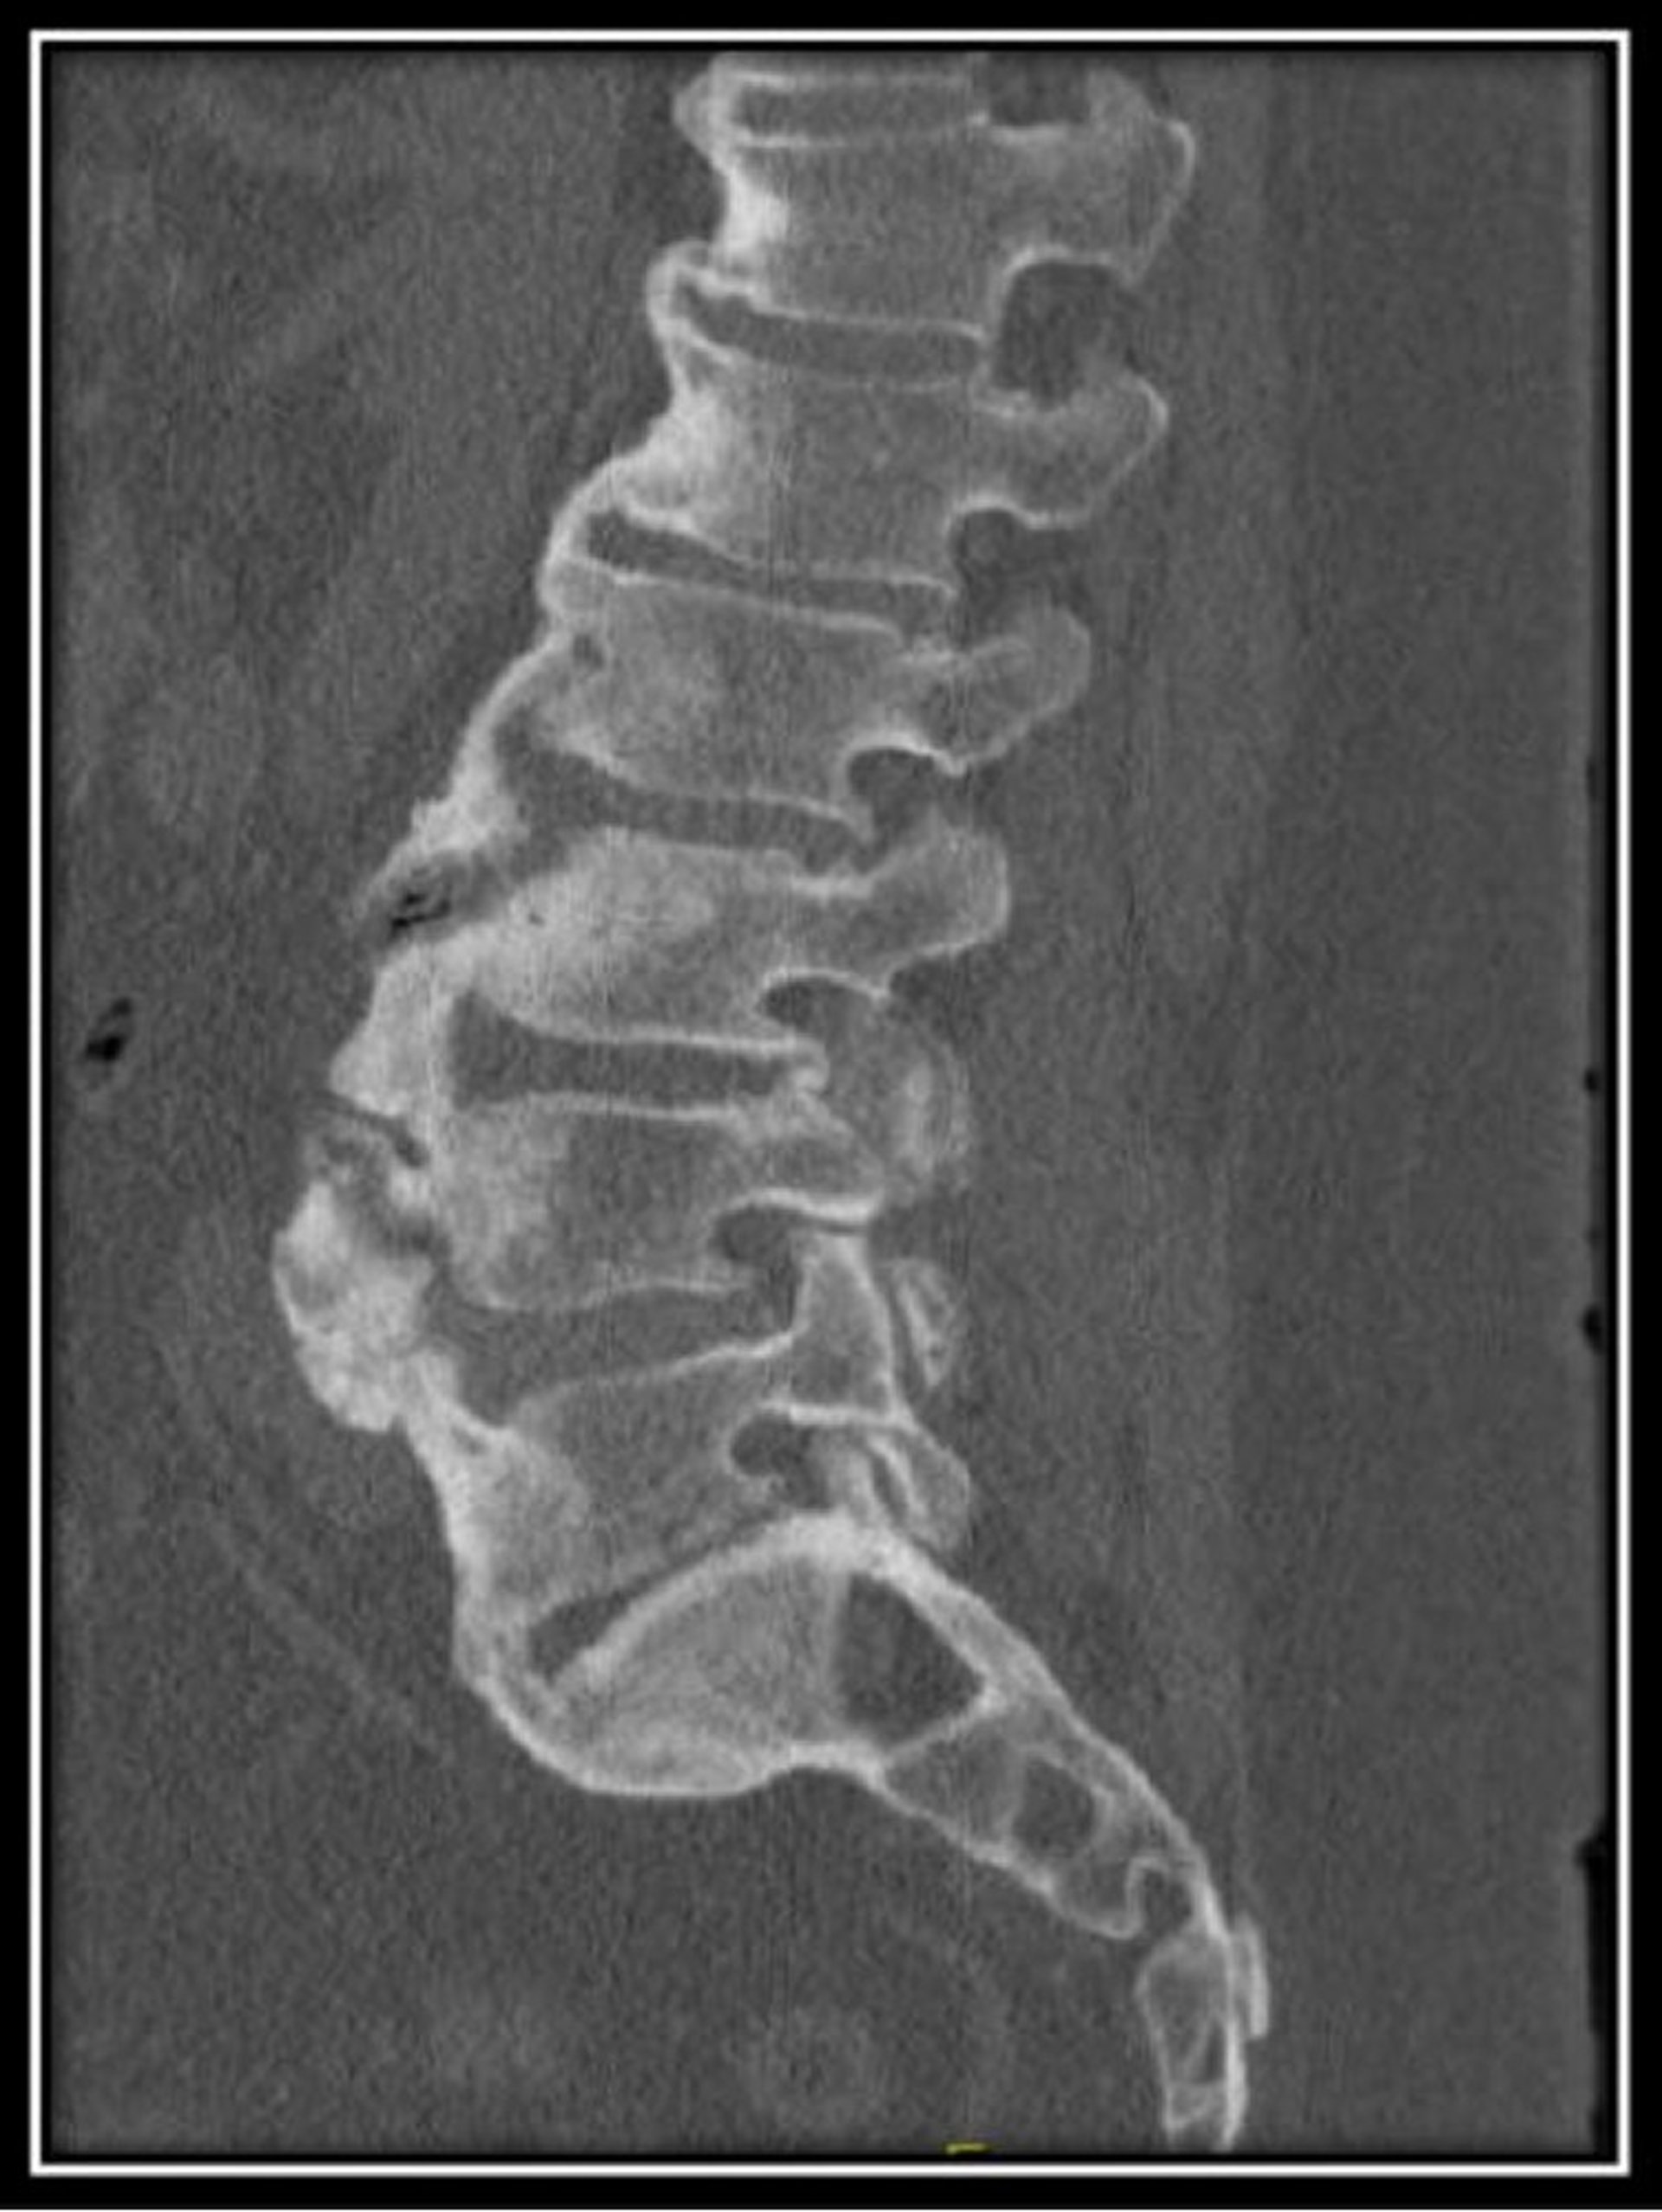

特徴的なX線上の変化には,椎体前方の広範な骨化(石灰化が,まるで誰かが脊椎の前方および側方にろうそくのろうを注いだかのように見える)があり,これは数個の椎骨を架橋する。

Image provided by Roy Altman, MD.

このびまん性特発性骨増殖症患者の腰椎CTでは,正常な椎体高とともに,前方に流れるようなびまん性の骨棘と維持された椎間板腔が認められる。

Image courtesy of Kinanah Yaseen, MD.

びまん性特発性骨増殖症(DISH):DISHは,主として50歳以上の男性に発生し,臨床およびX線所見が強直性脊椎炎と類似することがある。患者には,まれに脊椎の疼痛,こわばり,および潜行性の可動域減少がみられる。DISHのX線所見には,脊椎の靱帯前方の広範な骨化(石灰化が,まるで誰かが脊椎の前方および右側にろうそくのろうを注いだかのように見える)があるが,これは数個の椎骨(通常は椎体4個)を架橋し,通常は下位胸椎に始まり,やがて頸椎および腰椎を侵す。骨盤上口沿いおよび腱付着部(アキレス腱付着部など)に骨膜下の骨増殖がみられることが多い。しかし,脊椎前方の靱帯は正常でしばしば隆起し,仙腸関節および椎間関節にびらんはない。DISHの鑑別に有用となる付加的な特徴は,通常は朝に顕著にならないこわばり,および赤血球沈降速度正常値である。